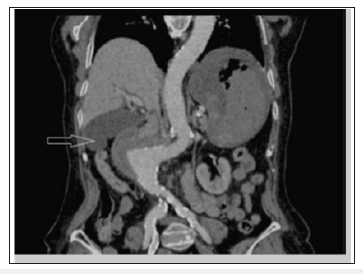

There are many modalities that may aid in the diagnosis of an AEF, but without strong clinical suspicion, these modalities may be futile. The initial evaluation of AEF should be started by esophagogastroduodenoscopy(EGD) to identify the cause of bleeding. The whole duodenum must be investigated in EGD because of the frequent location of the AEF in its 3rd and 4th parts. Findings suggestive of AEF on EGD include visible graft, bleeding, adherent clot, or ulcer or pulsatile mass (Figures 3 & 4). CT scan has 30-61% sensitivity in identifying PAEF, and 90% sensitivity and specificity in identifying SAEF. In addition to identifying the location, it may aid in the identification of an infection or abscess formation if present. Signs found on CT imaging may be gas shadow in or around the graft (sensitivity 40% and specificity 100%), focal wall inflammation and thickening, visible graft (sensitivity 22% and specificity 100%), soft tissue collection around the aorta (specificity 92% and sensitivity 90%), swelling or hematoma around the graft, intravenous contrast within the GI lumen or around the aorta, loss of calcification or tear in the aortic wall (specificity 75% and sensitivity 89%), pseudoaneurysm, and duodenal hematoma (Figures 5 & 6).

Figure 6:CT reconstruction: aneurysm with mass effect on the duodenum (arrow). Note the absence of the calcified atheroma on the right aortic contour that suggests aneurysmal rupture.

CT scan has 30-61% sensitivity in identifying PAEF, and 90% sensitivity and specificity in identifying SAEF. In addition to identifying the location, it may aid in the identification of an infection or abscess formation if present. Signs found on CT imaging may be gas shadow in or around the graft (sensitivity 40% and specificity 100%), focal wall inflammation and thickening, visible graft (sensitivity 22% and specificity 100%), soft tissue collection around the aorta (specificity 92% and sensitivity 90%), swelling or hematoma around the graft, intravenous contrast within the GI lumen or around the aorta, loss of calcification or tear in the aortic wall (specificity 75% and sensitivity 89%), pseudoaneurysm, and duodenal hematoma [21-23].